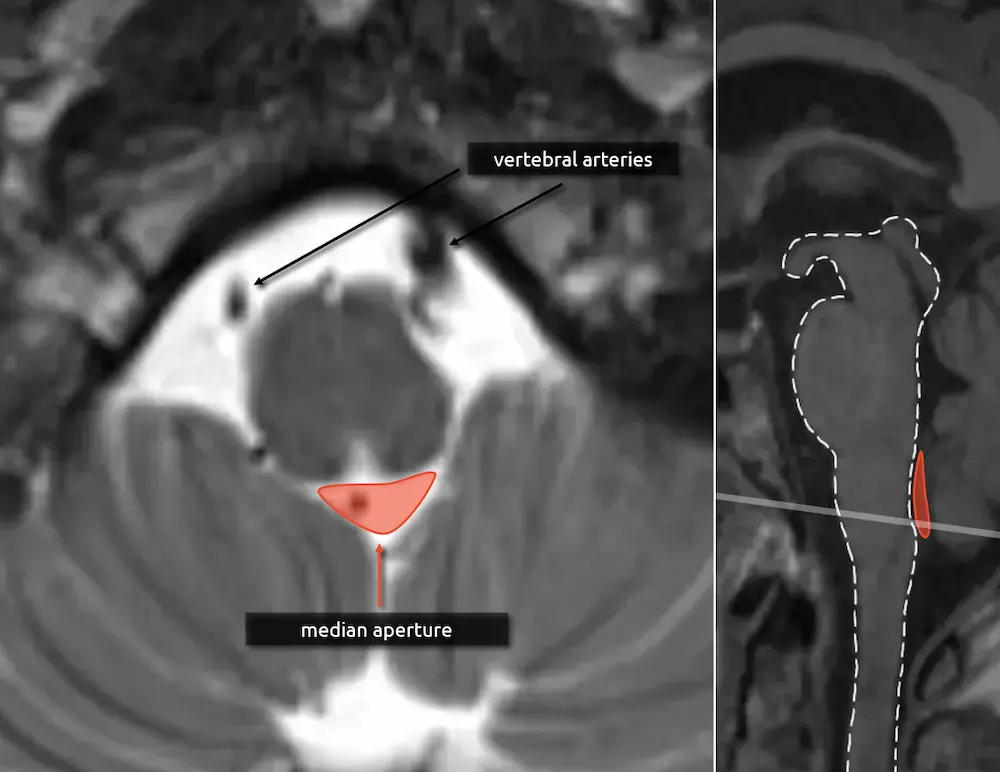

1. Median aperture

The median aperture, or the foramen of Magendie, is the thin CSF space posterior to the medulla and medial drainage pathway of the fourth ventricle. There are two more holes in the lateral aspect of the fourth ventricle, called the lateral apertures or foramina of Luschka. Together, these are the three ways that CSF can flow inferiorly into the cisterna magna.

2. Vertebral arteries

The vertebral arteries fuse to form the basilar artery approximately at the level of the upper medulla. If they are present, then you are likely at the level of the medulla in the absence of variant anatomy (e.g. basilar nonfusion).

The medulla gradually transitions to the shape of the cervical spinal cord. The median aperture does not significantly change along its course.